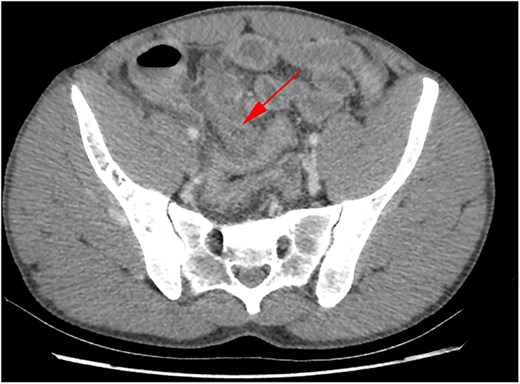

A thirty-year-old man with no chronic illnesses presented to the emergency department with a three-day history of generalized abdominal pain and vomiting. His surgical history was notable for a previous admission one year prior for Computed Tomographic (CT) scan confirmed uncomplicated acute appendicitis that was managed non-operatively. His current complaints included gradually worsening right lower quadrant pain that later became generalized. The history was also positive for multiple episodes of vomiting that contained previously ingested food and later bile-stained fluid. The patient also complained of loose, watery stool and progressive global abdominal distension. On the day before presentation, he experienced subjective fever with chills and rigors. Physical examination revealed abdominal distension with marked tenderness in the lower abdomen, guarding, and rebound tenderness, most pronounced in the right iliac fossa. No palpable masses or organomegaly were noted; bowel sounds were present but reduced. Cardiovascular, respiratory, and neurological examinations were normal. A CT scan of the abdomen and pelvis showed the following (Figs 1 and 2):

A dilated appendix measuring 1.6 cm in diameter with peri-appendiceal inflammatory changes. A 1.1 cm fluid focus with peripheral enhancement was seen, consistent with focal perforation.

A 10.9 cm (AP) × 7.2 cm (W) focus that appeared to arise from a loop of ileum, concerning for a giant small bowel diverticulum

CT abdomen/pelvis axial view demonstrating small bowel diverticulum.